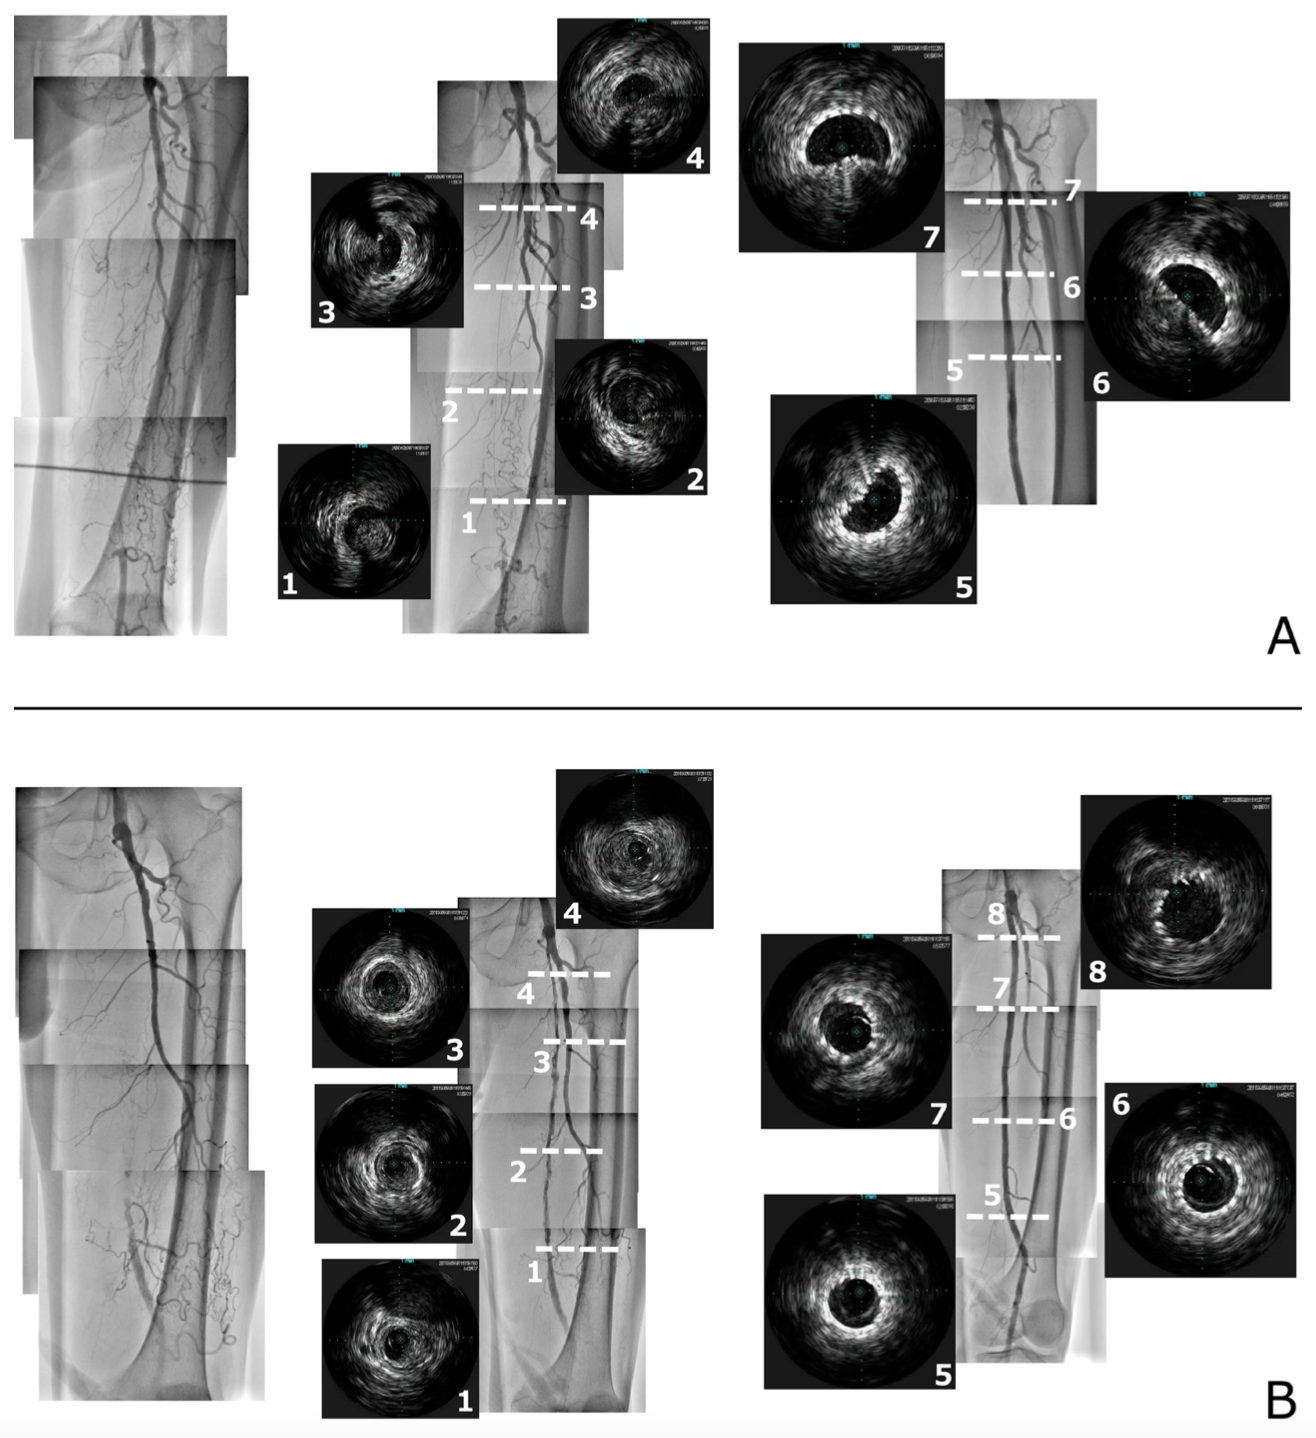

With the accumulation of experience and the developments in ultrasound technology, EVUSG became the first-line strategy from April 2012 at the hospital where the study cohort was extracted. EVUS machine (Aplio Series; Canon Medical Systems Corporation) using a 7-8 MHz linear probe was employed, and the image quality was set to obtain a clear image of the guidewire and arterial wall border. Figure 2 shows the details of the technical execution of EVUSG during SFA-CTO crossings. We started using EVUSG for SFA-CTO lesions in 2004 and the other details of the EVUS-guided CTO wiring procedure have been recently reported.9 If the antegrade approach failed, a retrograde approach from the popliteal or tibial artery was performed. The re-entry device was used in only 1 case in the AG group. The type of guidewire and support catheter used when crossing the distal cap of the CTO and other details of the devices during the EVT procedure are described below. Once the guidewire had passed through the CTO, the lesion was dilated with an optimal balloon (initial balloon dilation), which can cross the occlusion site and is smaller than the diameter of the distal reference vessel.

Representative cases from the AG and EVUSG groups are shown in Figure 3A and Figure 3B, respectively.